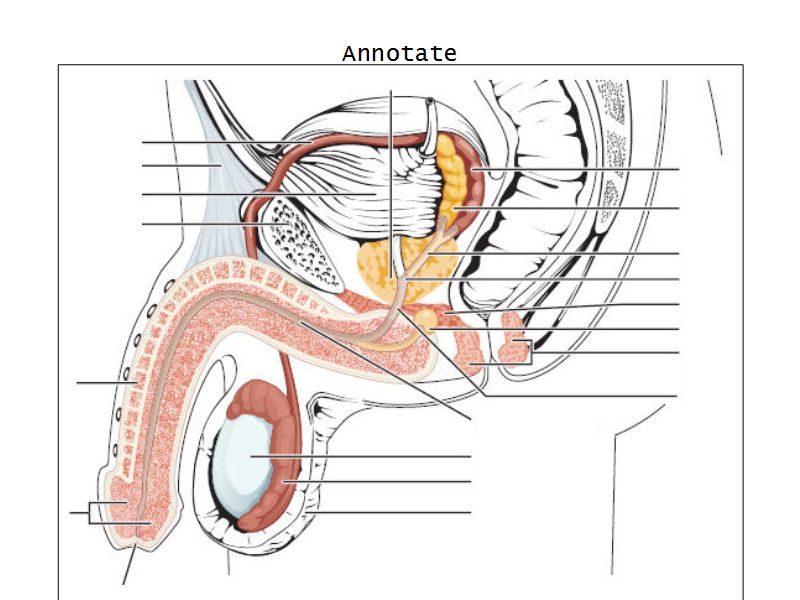

Penis

Slide 83Penis

- 3 cylindrical masses erectile tissue

- 2x corpora cavernosa

- 1x corpus spongiosum

- Surrounded by tunica albuginea

- Covered by skin

- Traversed by urethra

Tunica albuginea

- Fibrous connective tissue sheath

- Surround erectile bodies

- Dense collagen bundles

Corpora cavernosa

- Paired erectile bodies

- Irregular vascular spaces

- Lined with endothelium

- Trabeculae CT

- Smooth muscle cells

Corpus spongiosum

- Erectile body surrounding urethra

- More elastic fibres

- Few smooth muscle cells

- Vascular spaces uniform

- Glands

Glands of Littré

Present whole length of urethra